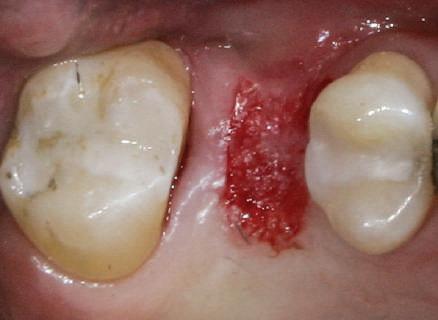

Reprepararea intraorală a bonturilor Acest pacient prezenta dentiţia maxilară compromisă, refuzând proteza mobilizabilă. Prin abordarea în etape, se menţin o parte din bonturile dentare naturale; s-a observat recesie în momentul amprentării pentru cel de-al doilea grup de implanturi.

Fig. 1 prezintă pacientul după inserarea primului set de bonturi implantare individualizate; dinţii naturali adiacenţi

sunt încă prezenţi pentru a susţine puntea provizorie.

Şapte luni mai târziu (fig. 2), acele bonturi individualizate din prima etapă au manifestat semne de recesie de 1-3mm. Atitudine: S-a decis reprepararea intraorală a tuturor bonturilor (fig. 3), astfel încât toate marginile bonturilor să fie la nivelul sau sub marginea gingivală (de notat că 1.1. şi 2.1. au fost submersaţi ulterior pentru a avea sprijin implantar deplin).

Deşi reprepararea a îmbunătăţit marcat estetica finală, a necesitat aplicarea şnurului de retracţie, amprente noi şi turnări noi.

Un caz separat dar similar ilustrează în figurile 4 și 5 reprepararea intraorală a bontului.

Cazul (1): Reprepararea intraorală a bonturilor Figurile

1. Aspect după inserarea primului set de bonturi implantare individualizate.

2. După 7 luni, bonturile individualizate din prima etapă au prezentat recesie de 1-3mm.

3. Bonturile repreparate intraoral.

Alt caz (1) Figurile

4. După osteointegrarea implantului 2.4., s-a observat recesia în etapa de amprentare a implantului 2.5.; s-a decis reprepararea marginilor bontului individualizat CAD/CAM 2.4. Înainte de preparare s-a aplicat şnur de retracţie pentru a evita lezarea ţesutului şi a îmbunătăţi vizibilitatea dintelui 2.3. şi a marginii bontului implantar individualizat. Aşa cum era de aşteptat, recesia a fost mai mare de-a lungul versantului distal al bontului 2.4. adiacent locului de extracţie vindecat/cu implantul mai nou.

5. Bontul individualizat aplicat (2.5.) cu bontul repreparat anterior (2.4.). Nu a survenit recesie nouă de o perioadă de peste 3 ani.